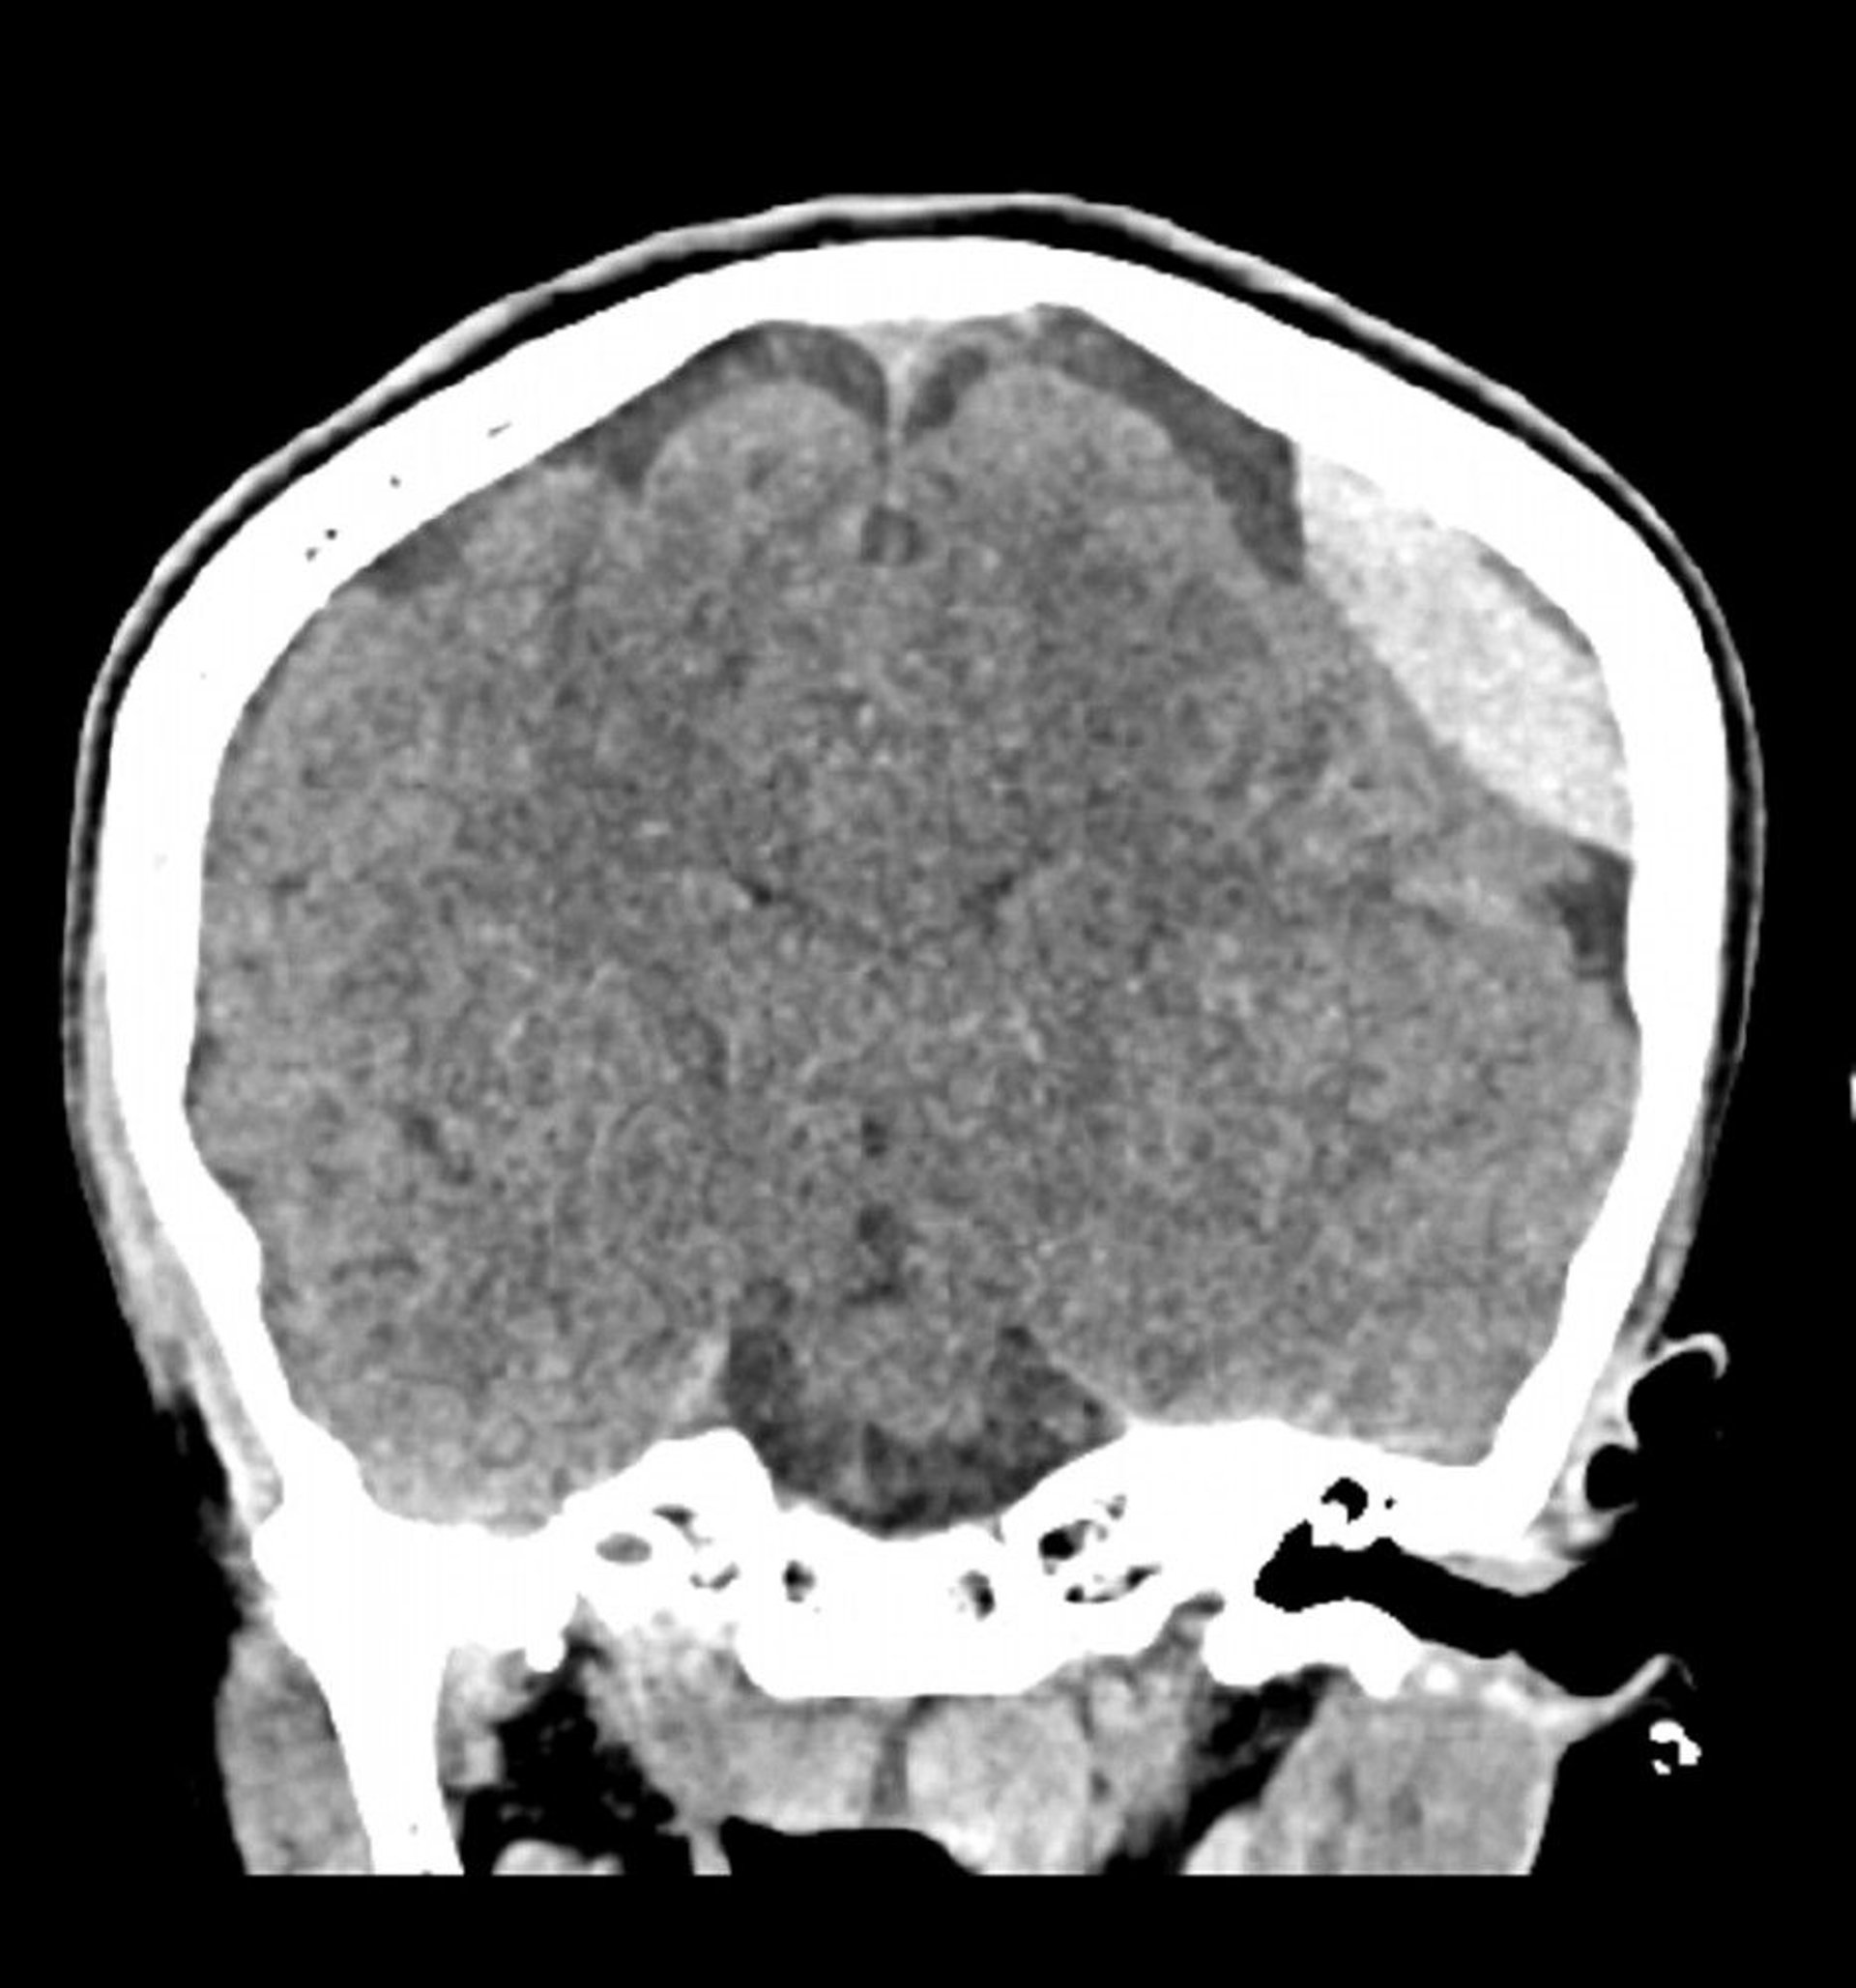

Epidural Hemorrhage (Coronal CT)

Classic lentiform (lens)-shaped hyperdensity that does not extend across suture lines.